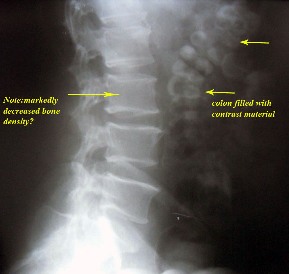

treatment. By difficulty we persuaded him to do ascending urography

" see photos".